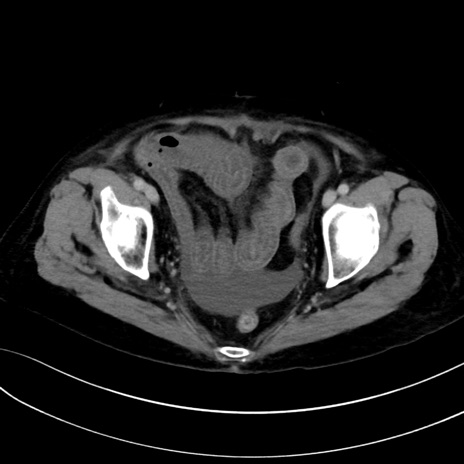

症例13 CT(横断像)1日半後

(冠状断像)1日半後